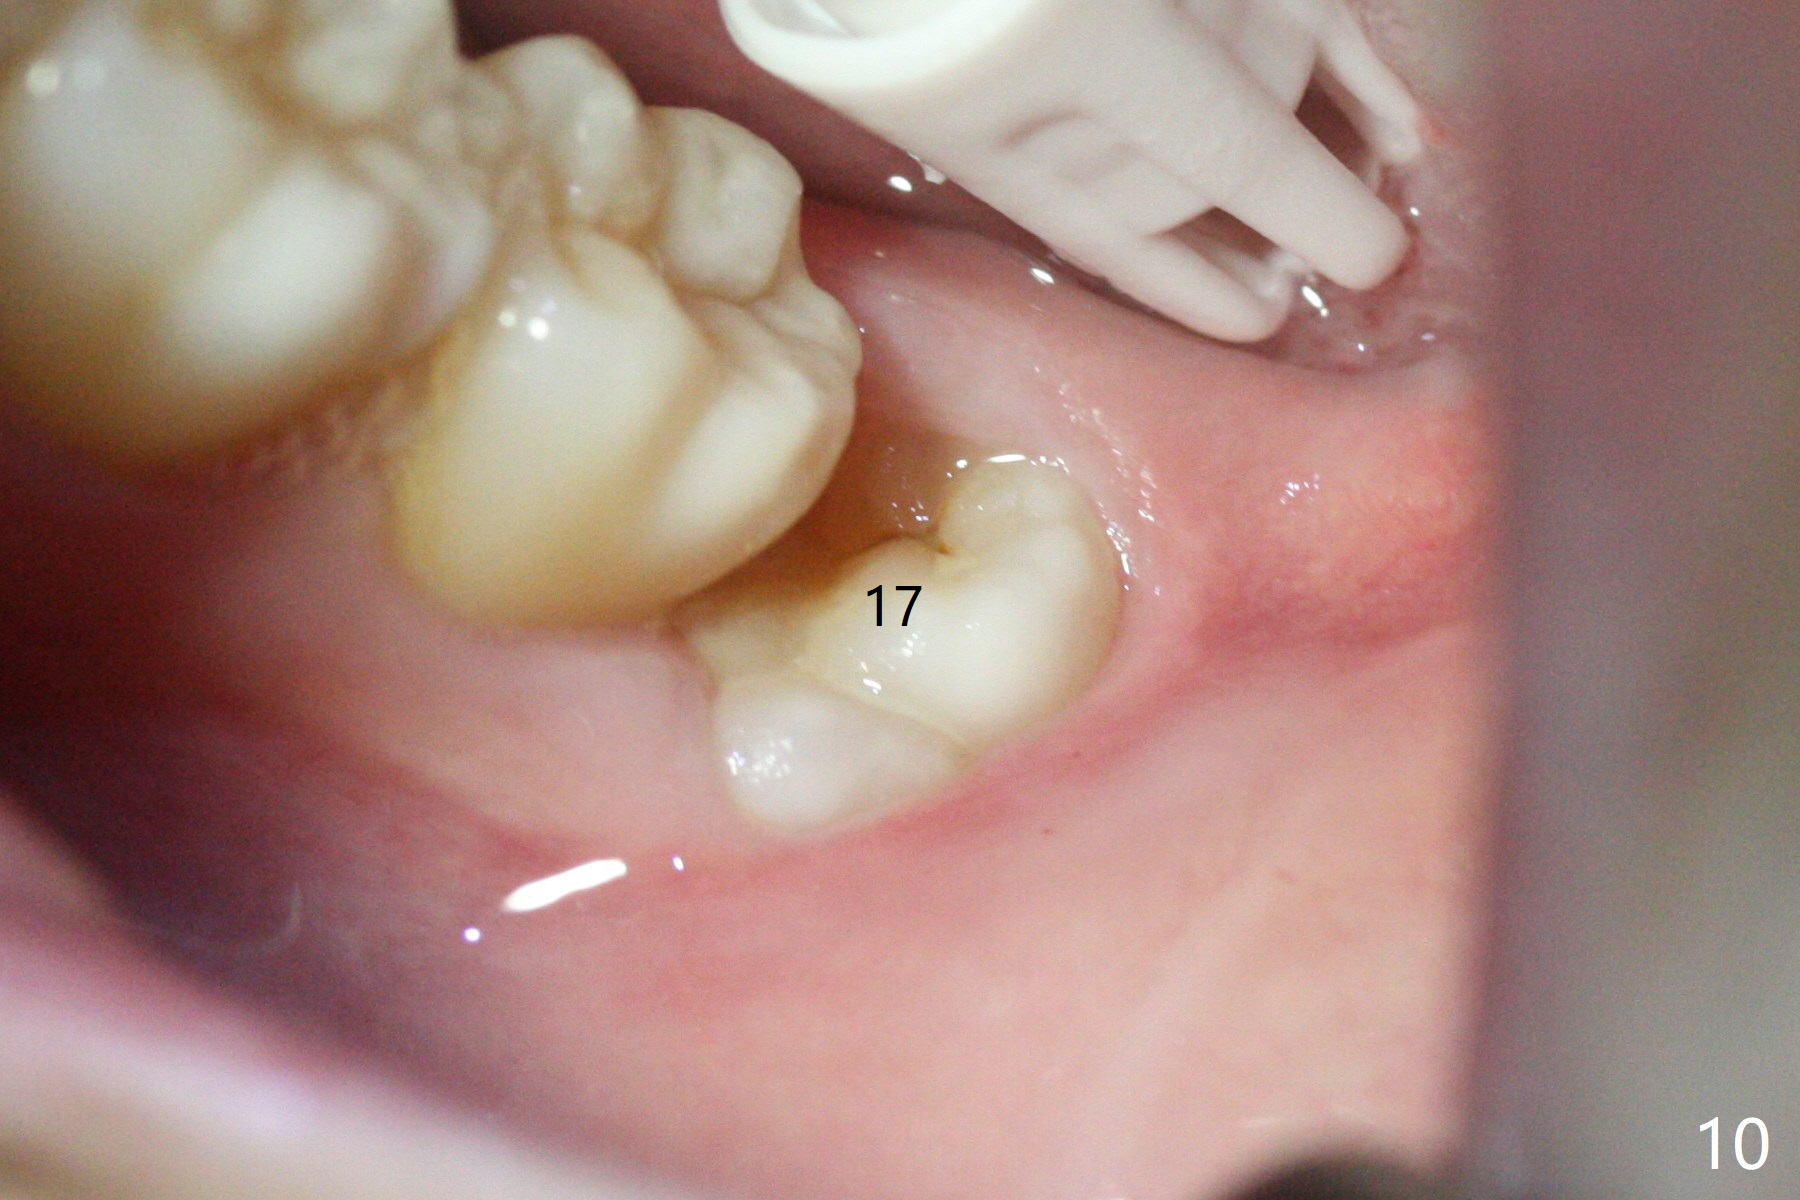

In fact the tooth #32 is extracted first; the defect involves the distobuccal aspect of the tooth #31 (Fig.4 *). An intraop PA is taken after extraction to confirm whether a broken surgical fissure bur tip retains or not; the distal lamina dura of #31 is low (Fig.5 *). It is expected to increase after cocktail bone graft (Fig.5' arrow). As planned, the bone cement (Fig.6 C) and allograft (G) are placed in the distal and mesial portions of the socket; between them is Osteogen Plug (O). Another piece of Osteogen Plug (as collagen membrane for bone graft) is placed on the top of the socket before suturing with 4-0 Plain Gut (Fig.7,7' O). Also note the bone graft being placed distobuccal (CT study) to #31 (Fig.7' red dashed line) to reduce possibility of future periodontitis. The patient returns 15 days postop with chief complaint of mild pain since extraction, although the wound looks normal. The transverse cortex connecting to the lamina dura (Fig.5 *) is obliterated when allograft is placed (Fig.7 G). The part of the graft remains in place 1 month postop (Fig.9) in spite of wound dehiscence (Fig.8). The bone graft loss is indicated by the fact of the reappearance of the transverse cortex (Fig.9). In the same appointment, the tooth #17 (Fig.10) is being extracted (Fig.11), leaving a defect mesiobuccal (Fig.12 *) to distal (curette). Part of Osteogen plug (Fig.13 O) is stretched to cover the mesially placed allograft (Fig.14 G). One quarter of Collagen plug is placed over the Osteogen plug (Fig.13 O) before 4-0 PGA suturing. There is bone regeneration 1 year postop (Fig.15,16).